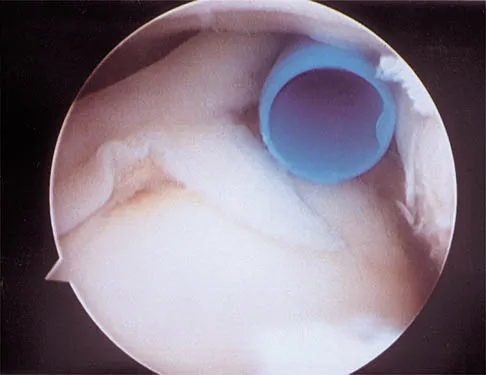

A 21-year-old collegiate pitcher has had pain in his dominant shoulder for the past 3 months despite management consisting of rest, rehabilitation, and an analysis of throwing mechanics. An arthroscopic photograph from the posterior portal is shown in Figure 10. The biceps anchor to the bone was not detached to probing. Treatment of the lesion to the left of the cannula should consist of arthroscopic

The lesion is a variation of a type I superior labrum anterior and posterior lesion; therefore, appropriate treatment is simple debridement. Biceps tenodesis or release is not indicated because the biceps tendon and anchor are intact. There is no indication for labral repair or capsulorraphy. Beaty JH (ed): Orthopaedic Knowledge Update 6. Rosemont, IL, American Academy of Orthopaedic Surgeons, 1999, pp 261-270.